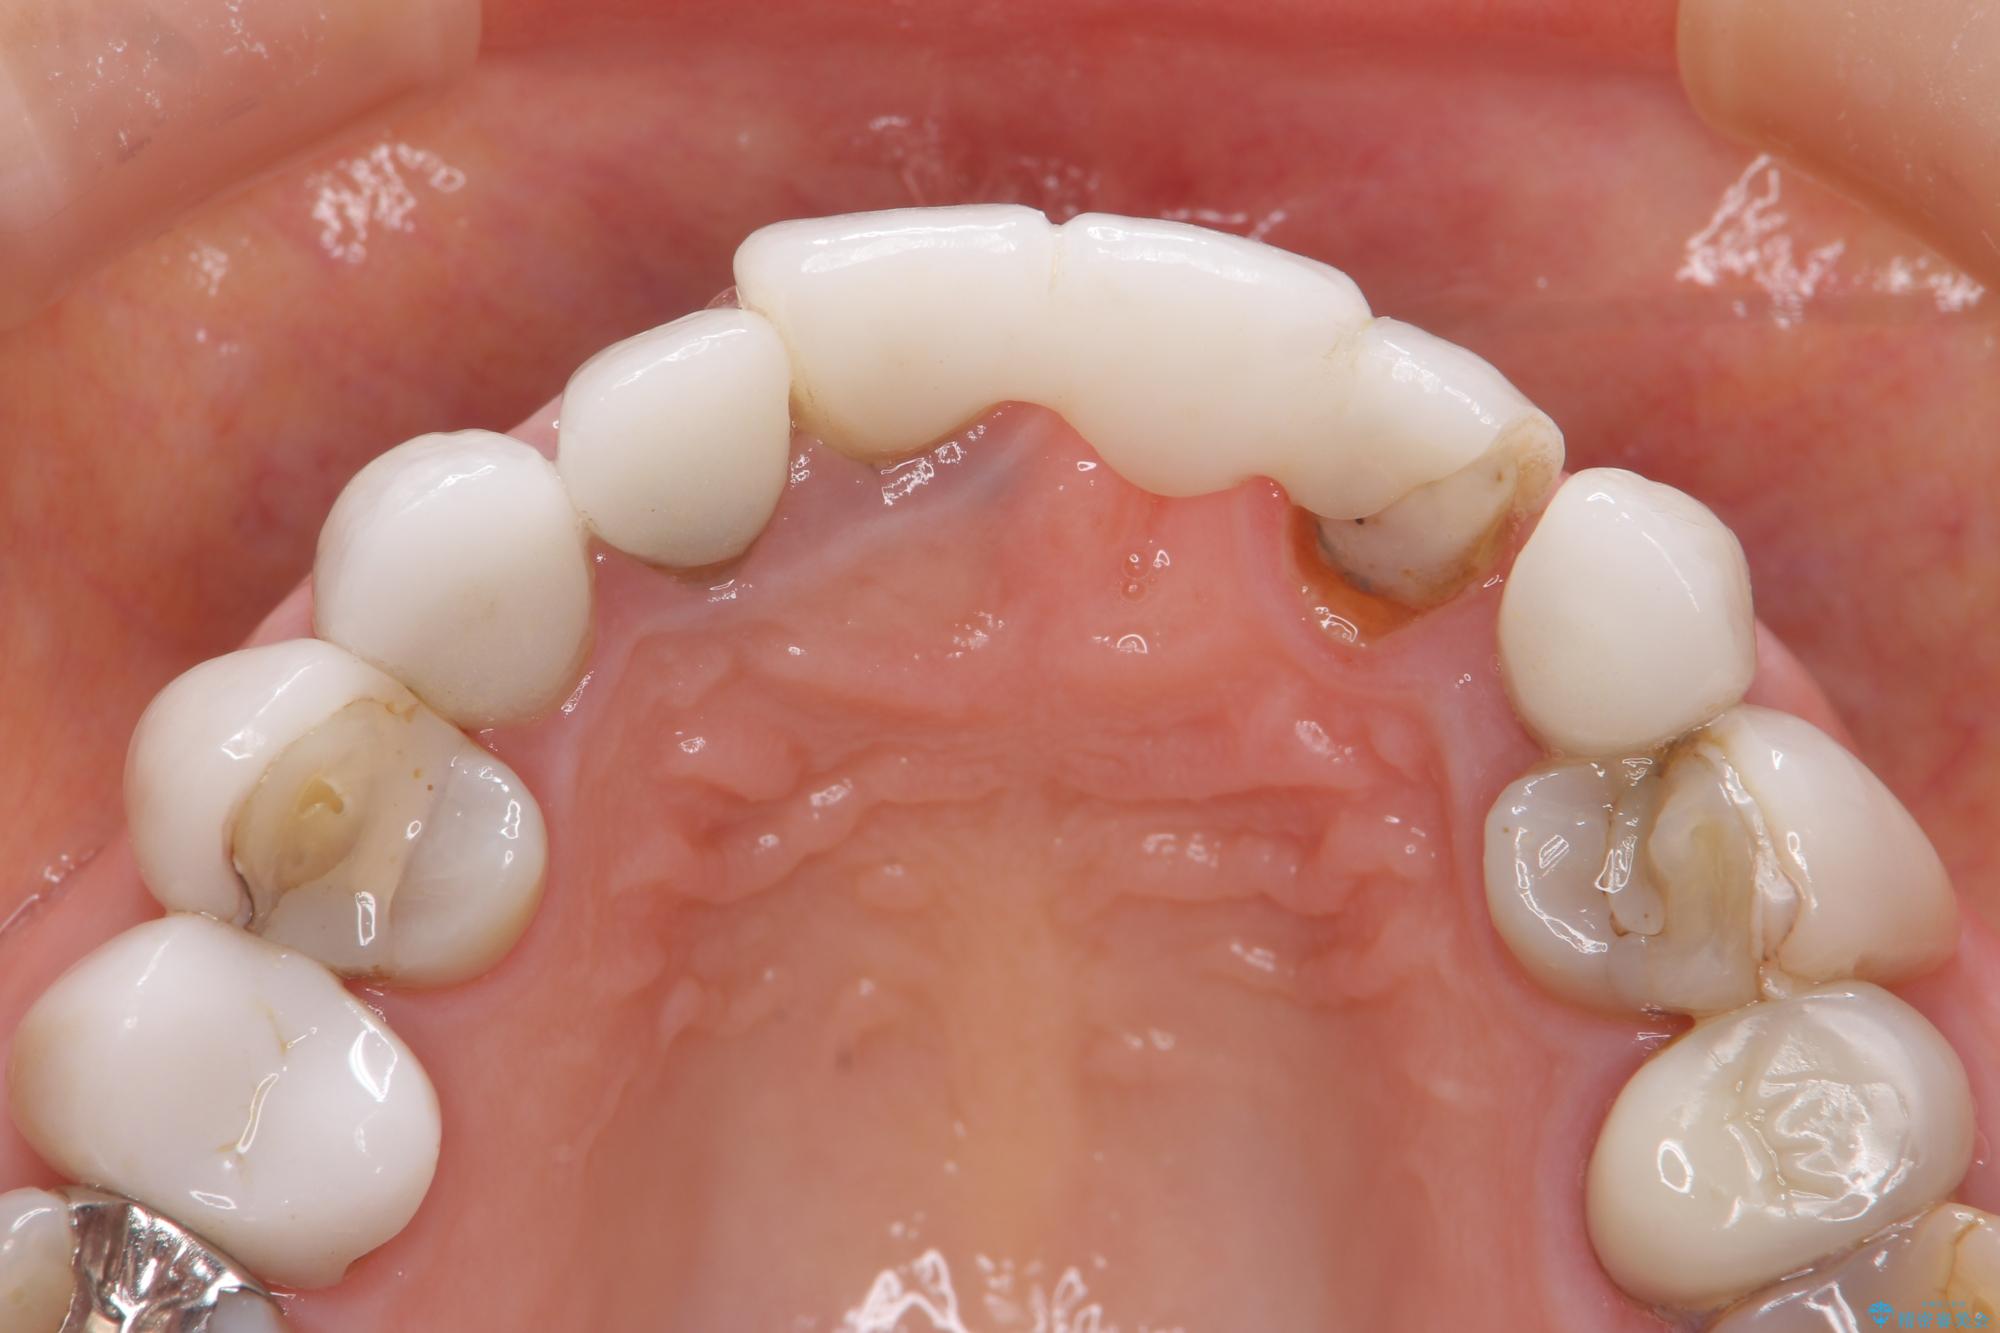

[ セラミック治療 ] 歯ぐきの際の黒ずみを改善したい

クラウンマージンの再設定を行うことで、黒ずんだ部分を再度覆い、審美障害を改善します。

- 52.8万円(ジルコニアクラウン×4・仮歯×4)費用は治療当時の料金となります